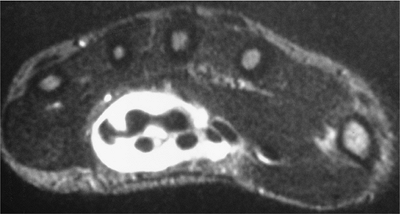

FIGURE 9-43 Lipoma. Axial (A) and sagittal (B) T1-weighted images of a lobulated fatty lesion (arrows) characteristic of a lipoma.